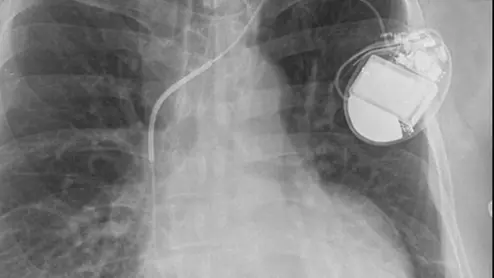

An implantable cardioverter defibrillator (ICD) and its associated leads viewed on a X-ray. Old leads are often abandon in veins and new ones added, but a new study of 1 million patients at ACC22 showed there is higher mortality if a device becomes infected and the leads are left behind. Image from RSNA.

Sean Pokorney, MD, director of the arrhythmia core lab, Duke Clinical Research Institute, assistant professor of Medicine, Duke University, discusses a late-breaking ACC 2022 study that shows mortality is higher in patients with implantable electrophysiology (EP) device infections where the leads are not explanted.